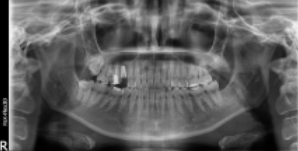

우측 엑스레이 보시면, 치아 뿌리가 남아있는 상황으로 '치아 뿌리 발치'가 먼저 필요한 상황이었습니다. 방치하게 되면, 통증이 더 심해질 수 있기에 빠르게 발치를 먼저 진행하셨습니다.

수술 후의 사진입니다. 가장 먼저 임플란트에서 치아의 '기둥' 역할을 하는 픽스처를 식립하였고, 그 후 지주대, 인공치근까지 치료가 완료되었습니다.

기존에 교체가 필요한 골드크라운도 올 세라믹 크라운으로 함께 진행하여 저작 능력과 심미성 두 마리의 토끼를 다 잡는 방향으로 치료가 진행되었습니다.

전체 치료 기간은 약 3개월 정도 소요되었습니다. 환자분이 치과치료 통증에 대한 걱정과 두려움이 많으셨는데, 무사히 치료가 마무리된 후 '원장님, 생각했던 것보다 괜찮았습니다. 참을만했어요.'라고 말씀을 해주셨던 기억이 납니다.